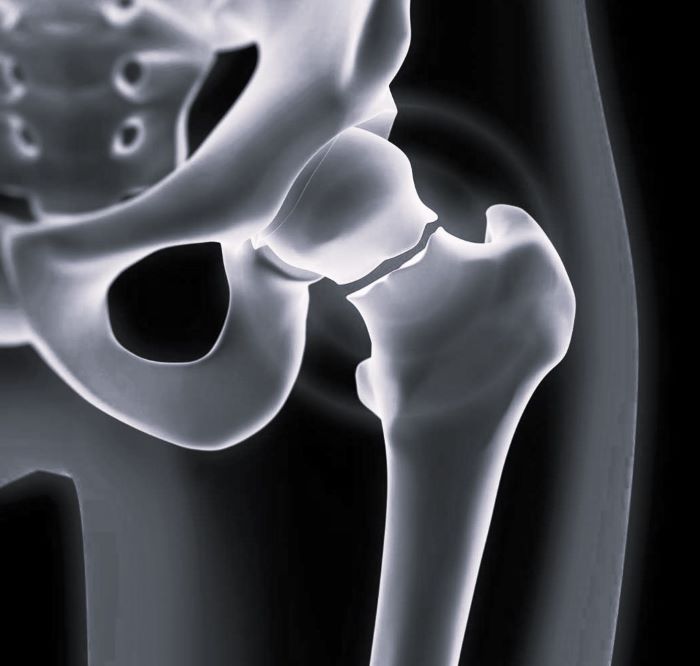

Шейка таза перелом

Шейка таза перелом 111 фото